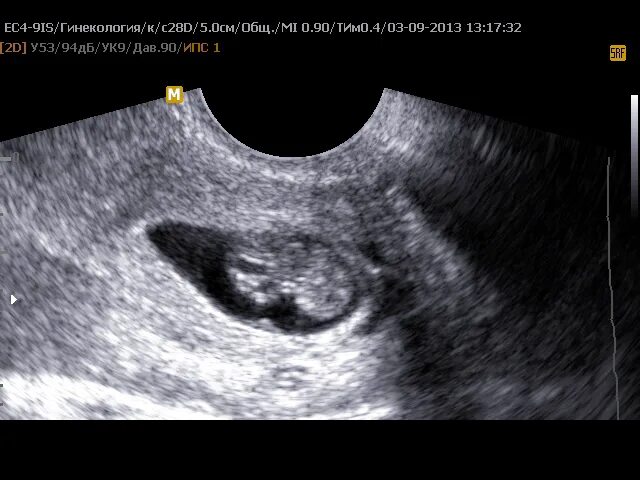

Плодное яйцо и эмбрион форум